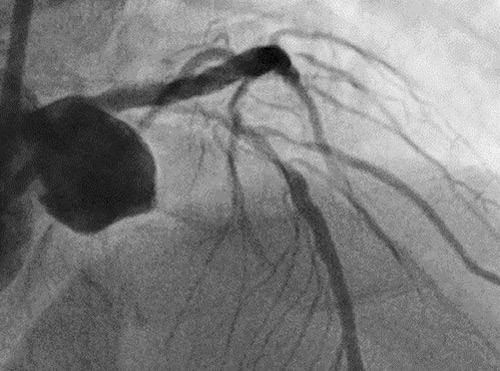

Diagnostic angiography

RCA shows diffuse atherosclerosis stenosis lesion, especially at the ostium.

The left coronary artery indicated 90% stenosis with severe calcification from the proximal to the middle part of LAD and diagonal branch